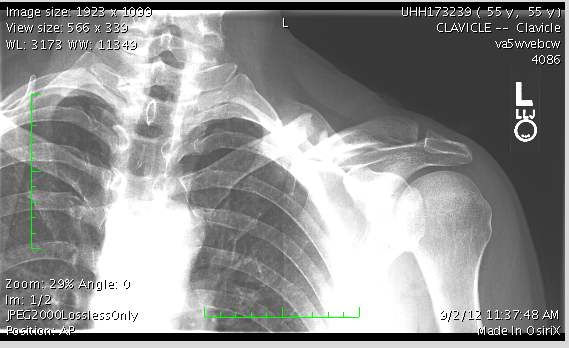

Because imagine, if you sprain your ankle running or bust a collarbone on the weekend group ride, you’re at the mercy of the very system you dared to criticize. Then anything can happen.